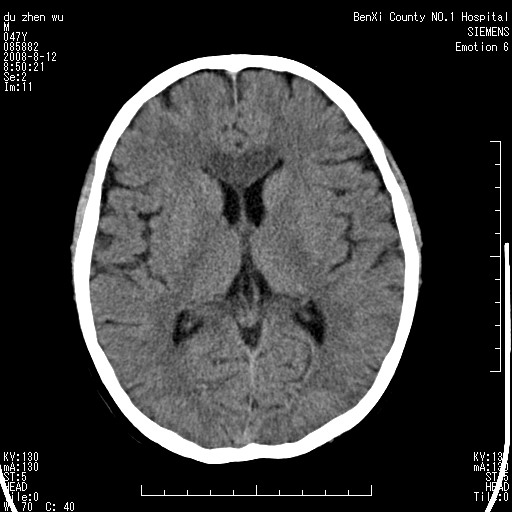

标题: CT15142:M47Y,胼胝体低密度病变 [打印本页]

标题: CT15142:M47Y,胼胝体低密度病变

男、时有神智不清,头晕,能正常回答问题,无肢体偏瘫

考虑胼胝体变性(脱髓鞘病变),找到一篇论文

典型,支持 胼胝体变性(脱髓鞘病变

支持 胼胝体变性-----常见于酒精中毒患者